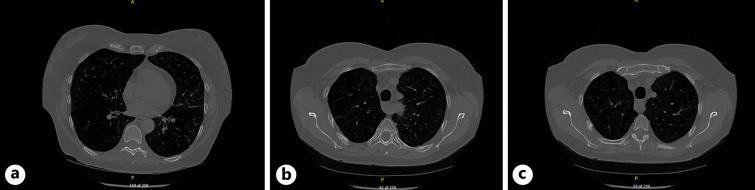

A 62-year-old woman with a 40-pack-year smoking history and severe chronic obstructive pulmonary disease with early-stage right upper lobe non-small cell lung cancer (NSCLC) was treated with stereotactic ablative radiotherapy (SABR). Two years after treatment, a surveillance computerized tomography scan showed lesions of the posterior 4th and 5th ribs including expansion of the medulla that was unusual and of concern for possible malignant infiltration. A follow-up magnetic resonance imaging (MRI) scan revealed these lesions to be healing fractures post-radiotherapy. Although generally well tolerated, SABR is known to produce inflammatory and fibrotic changes both in-field and in organs at risk, and rib fractures are a well-established adverse event. MRI has high diagnostic accuracy and sensitivity for rib fractures and was able to rule out malignant spread. This case demonstrates the need for regular follow-up following SABR for early-stage NSCLC, as well as the challenge of interpreting indeterminate post-SABR radiography findings.

一名62岁女性,有40年的吸烟史,患有严重的慢性阻塞性肺疾病,同时患有早期右肺上叶非小细胞肺癌(NSCLC),接受了立体定向消融放疗(SABR)。治疗两年后,一次监测计算机断层扫描显示第4和第5后肋有病变,包括髓质扩张,这种情况不常见,且担心可能存在恶性浸润。后续的磁共振成像(MRI)扫描显示这些病变为放疗后的愈合性骨折。尽管SABR通常耐受性良好,但已知其会在照射野内和危及器官中产生炎症和纤维化改变,肋骨骨折是一种公认的不良事件。MRI对肋骨骨折具有较高的诊断准确性和敏感性,能够排除恶性扩散。该病例表明,对于早期NSCLC患者,SABR治疗后需要定期随访,同时也说明了解读SABR后不确定的影像学检查结果所面临的挑战。